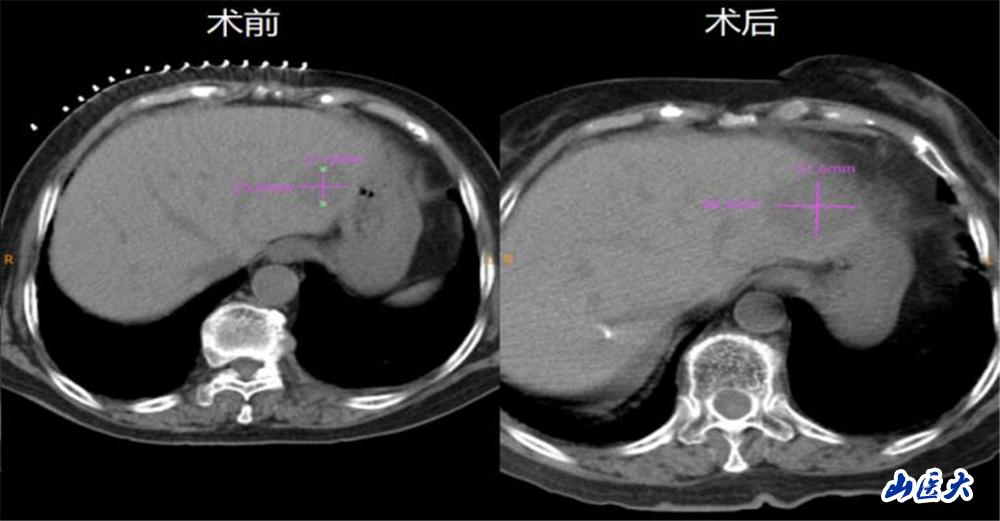

患者为一名93岁女性,确诊直肠恶性肿瘤一年,在当地医院行药物治疗,并定期复查。近期复查CT提示,直肠病变较前缩小,肝S2及S6转移结节明显增大。患者在我校第二医院肿瘤科住院后,继续完善核磁等检查,对比以往影像学检查显示,肝S2及S6转移结节有不均匀强化,较前明显增大。

在介入手术室魏臻护士长带领的护理团队配合下,肿瘤科微创治疗团队成功为该患者进行了CT引导下经皮肝S2段转移瘤微波消融治疗。对比术前术后CT,消融范围明确,且超出原并发灶边缘5mm以上,达到了完全消融的效果。